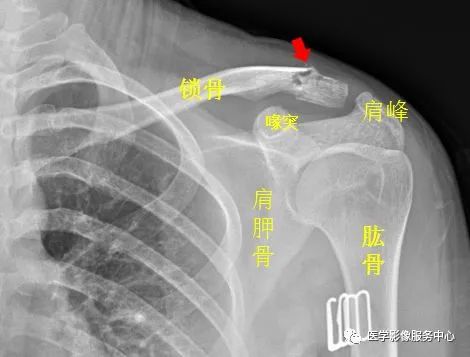

(五)肩关节

右侧肱骨大结节骨皮质欠光整,见弧形透亮线。右侧肱骨大结节骨折。

左侧锁骨肩峰端见不规则透亮线,骨折处稍移位,左侧锁骨骨折。